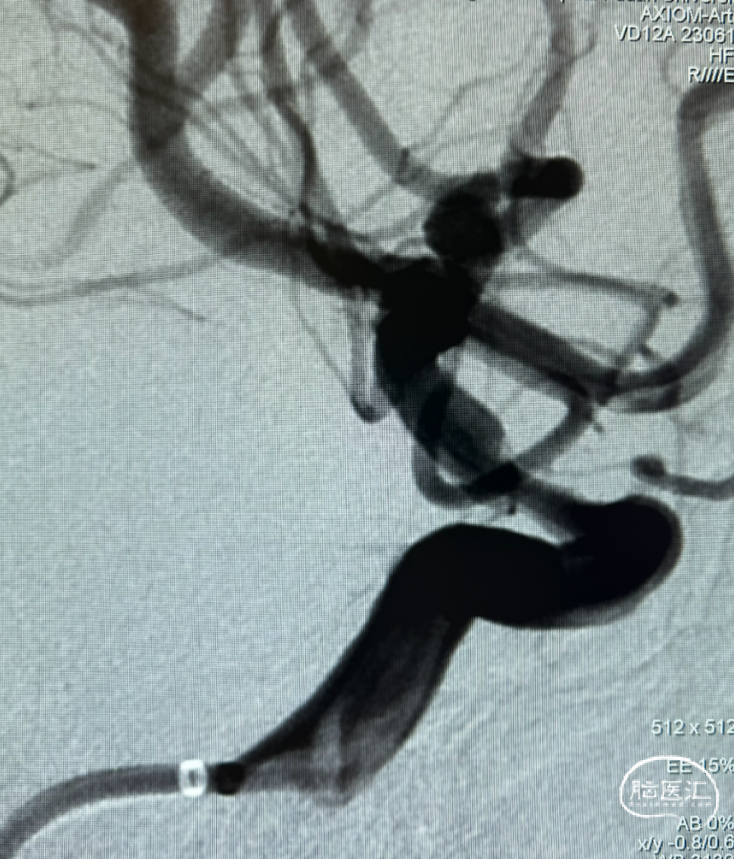

三维旋转图像:左侧大脑中动脉早额支起始部囊性动脉瘤。

动脉瘤参数:最大径4.4mm,瘤高3.5mm,瘤颈宽3.5mm,载瘤动脉直径1.3mm。

工作角度造影。

解脱后工作角度即刻造影,早额支及主干未受影响,动脉瘤内已可见血流分层。

术后三维重建及WEB™融合后图像,可见WEB™贴壁良好。

本例患者为左侧大脑中动脉早额支与M1主干分叉部动脉瘤,其解剖特点显著不同于常见分叉部动脉瘤,动脉瘤瘤颈主体位于早额支,该载瘤早额支细小且与大脑中动脉M1主干成角明显,大脑中动脉M1段自身亦在动脉瘤部位向上成角,导致血管构筑和血流动力学复杂化。如选择常规支架辅助弹簧圈治疗,支架不能满意打开,支架内血栓形成的风险大大增加。故WEB™ 17自膨式动脉瘤瘤内栓塞器治疗是较为合适的介入治疗方案。术前三维重建显示动脉瘤最大径4.4mm,形态相对规则,但成角的存在使微导管塑形成为关键。对于成角显著者,需谨慎评估术中通路建立的可行性及装置稳定性,风险过高可考虑M1主干内血流导向装置植入或外科夹闭进行个体化决策。